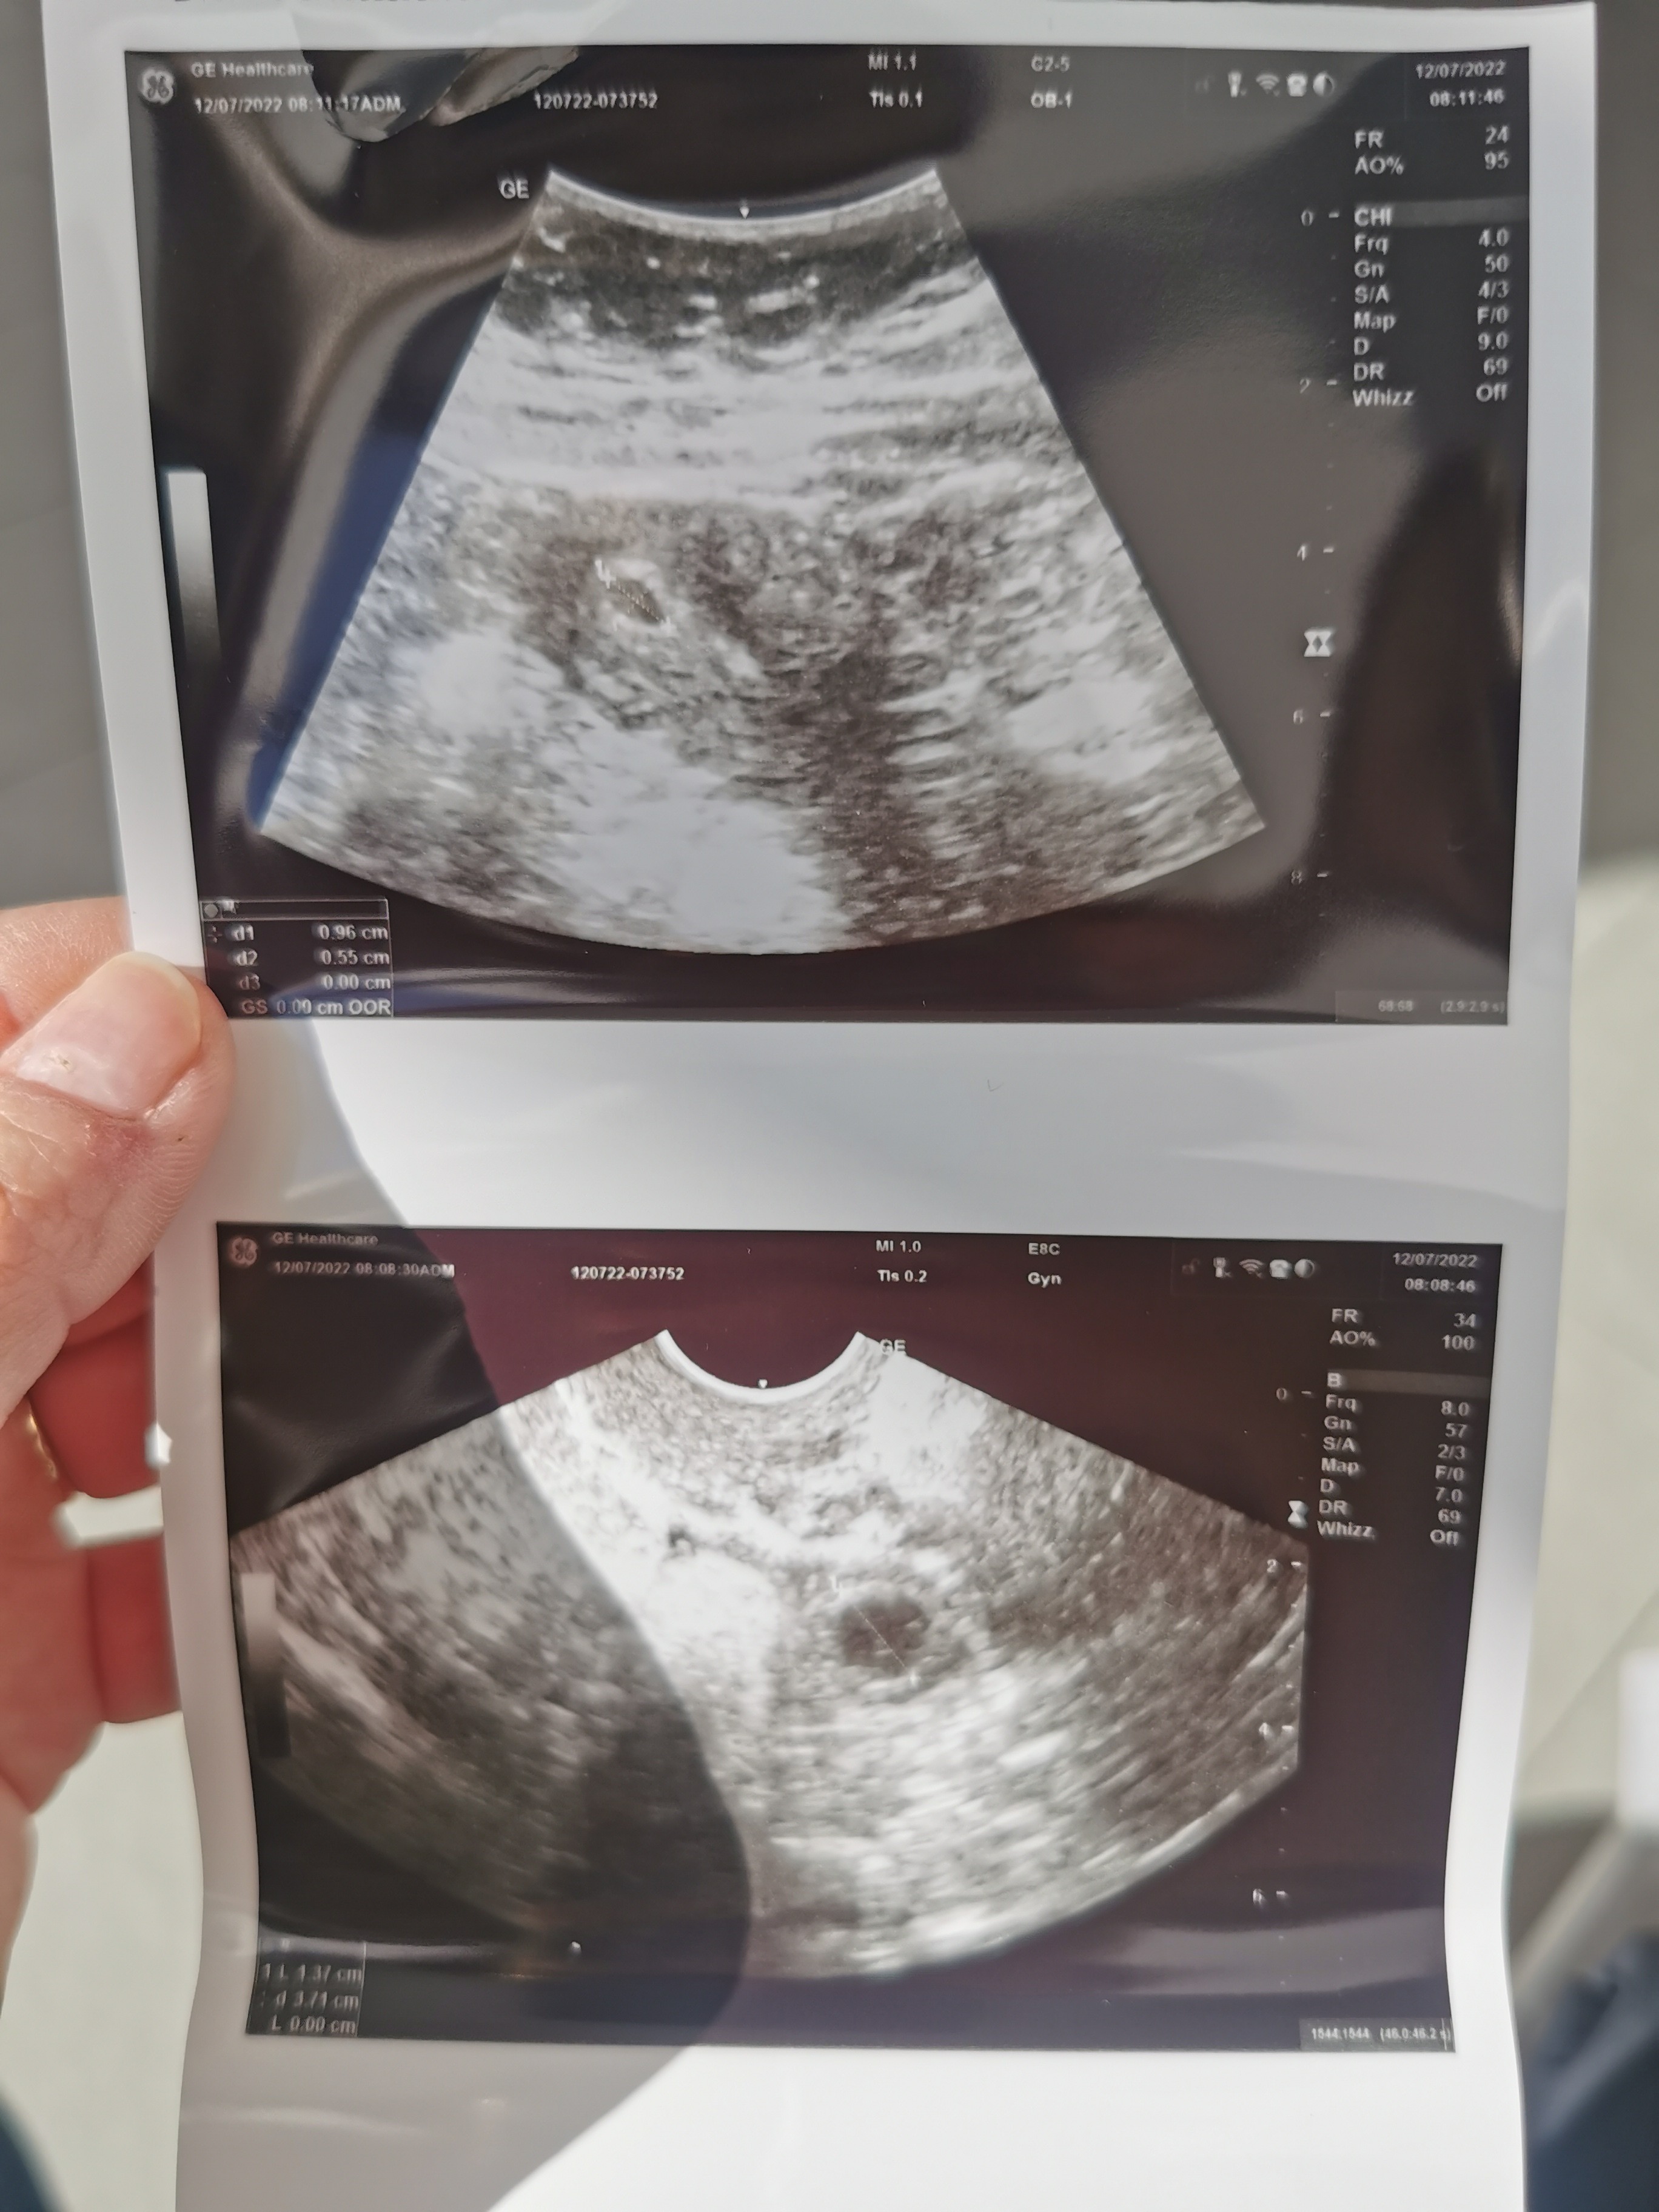

Dziewczyny, byłam dziś u ginekologa. Najpierw transwaginalnie nie mógł znaleźć nic, nawet jajnika. Mówił, że ma nowe usg i nie wie do końca jak je obsłużyć. 🙈

W końcu zrobił mi przez brzuch i coś znalazł, ale mówił, że nie wie co to jest. Być może ciąża maciczna a być może ciąża pozamaciczna. Kazał przyjść jutro przed 8 rano na kolejne usg. I zrobiłam dziś betę.

• IMG_20220712_082122.jpg

IMG_20220712_082122.jpg

1 001,9 KB · Wyświetleń: 108